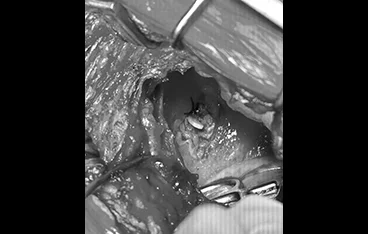

📍 흉관장착

흉관장착 전

흉관장착 후

정확한 진단과 수술로 삶의 질을 회복합니다